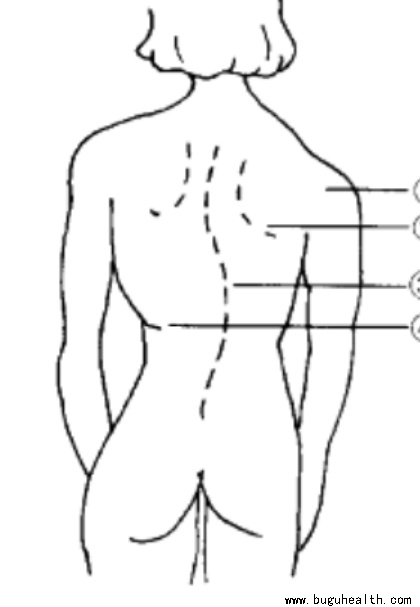

- 据统计,目前我国脊柱侧弯患者超300万,并以每年30万的速度递增,其中超过半数为青少年。脊柱侧弯成为继肥胖症、近视之后,我国儿童青少年健康的第三大“杀手”。.....

- 青少年特发性脊柱侧弯的现状:青少年骨科疾病发病率居首位,青少年脊柱侧弯发病率3%-5%,其中80%以上发生在女孩子身上。据相关统计,我们目前大概有500多万青少年脊柱侧弯患者,并且以30万/年的速度递增。.....

- 据统计,目前我国脊柱侧弯患者超300万,并以每年30万的速度递增,其中超过半数为青少年。脊柱侧弯成为继肥胖症、近视之后,我国儿童青少年健康的第三大“杀手”。要知道,脊柱侧弯不仅影响体型,更重要的是会导致严重的身体健康问题。 .....

- 有大约80%脊柱侧弯的发病原因还没有得到确定,因为它是由很多因素引起的。青少年的脊柱侧弯大部分是特发性脊柱侧凸,可能会和遗传、神经系统异常、骨骼生长异常、激素和代谢功能障碍、生物力学因素等有关,还可能与环境及生活方式等有关。.....

- 脊柱侧弯,顾名思义是指脊柱的侧向弯曲,同时会伴有胸部的扭曲、椎体的旋转。引起脊柱侧弯的原因有很多,包括遗传倾向,激素影响,脊椎与脊髓生长不协调,引起脊柱不对称生长和中枢神经系统的改变皆有可能,但并不足以充分解释发病原因。因此,大部分脊柱侧弯成因并不明确,故称为特发性脊柱侧弯,而一般在青少年时期(约1.....